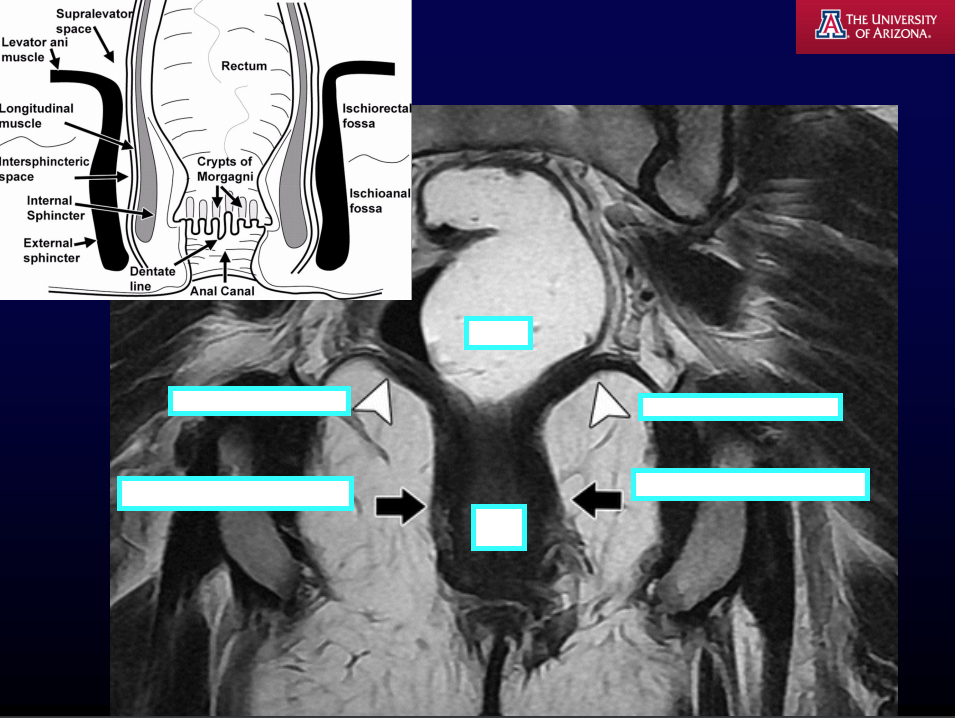

MRI T2WI fat is [] and fluid is [].

MRI T2WI fat is bright and fluid is bright.